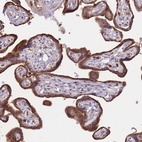

Immunohistochemical staining of human placenta shows strong cytoplasmic positivity in trophoblastic cells.